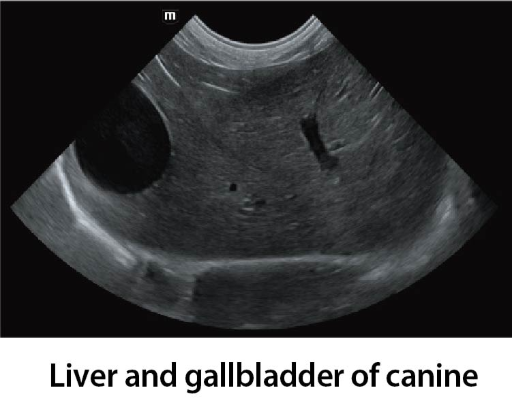

Клинични снимки

Clinical Images